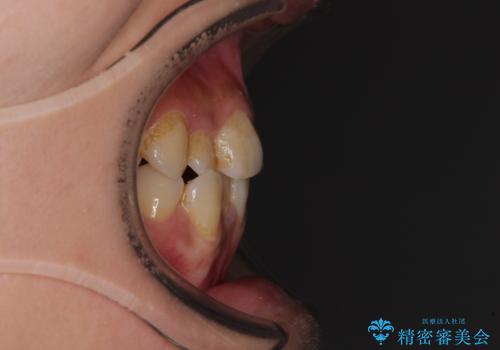

前歯のデコボコとクロスバイト インビザラインによる矯正治療

- 上下のクロスバイトと前歯のデコボコを気にして来院された患者様です。

骨格的に下顎がやや前方にあり、奥歯にクラウンが装着されているため、矯正治療後半の不安定な咬み合わせを避けるのであればワイヤー矯正がおすすめとなりますが、希望によりインビザラインにて治療を行うこととしました。

懸念されたとおり、右下のクラウン部分が全く咬み合わず、仕上げの段階で治療期間が長くなりました。